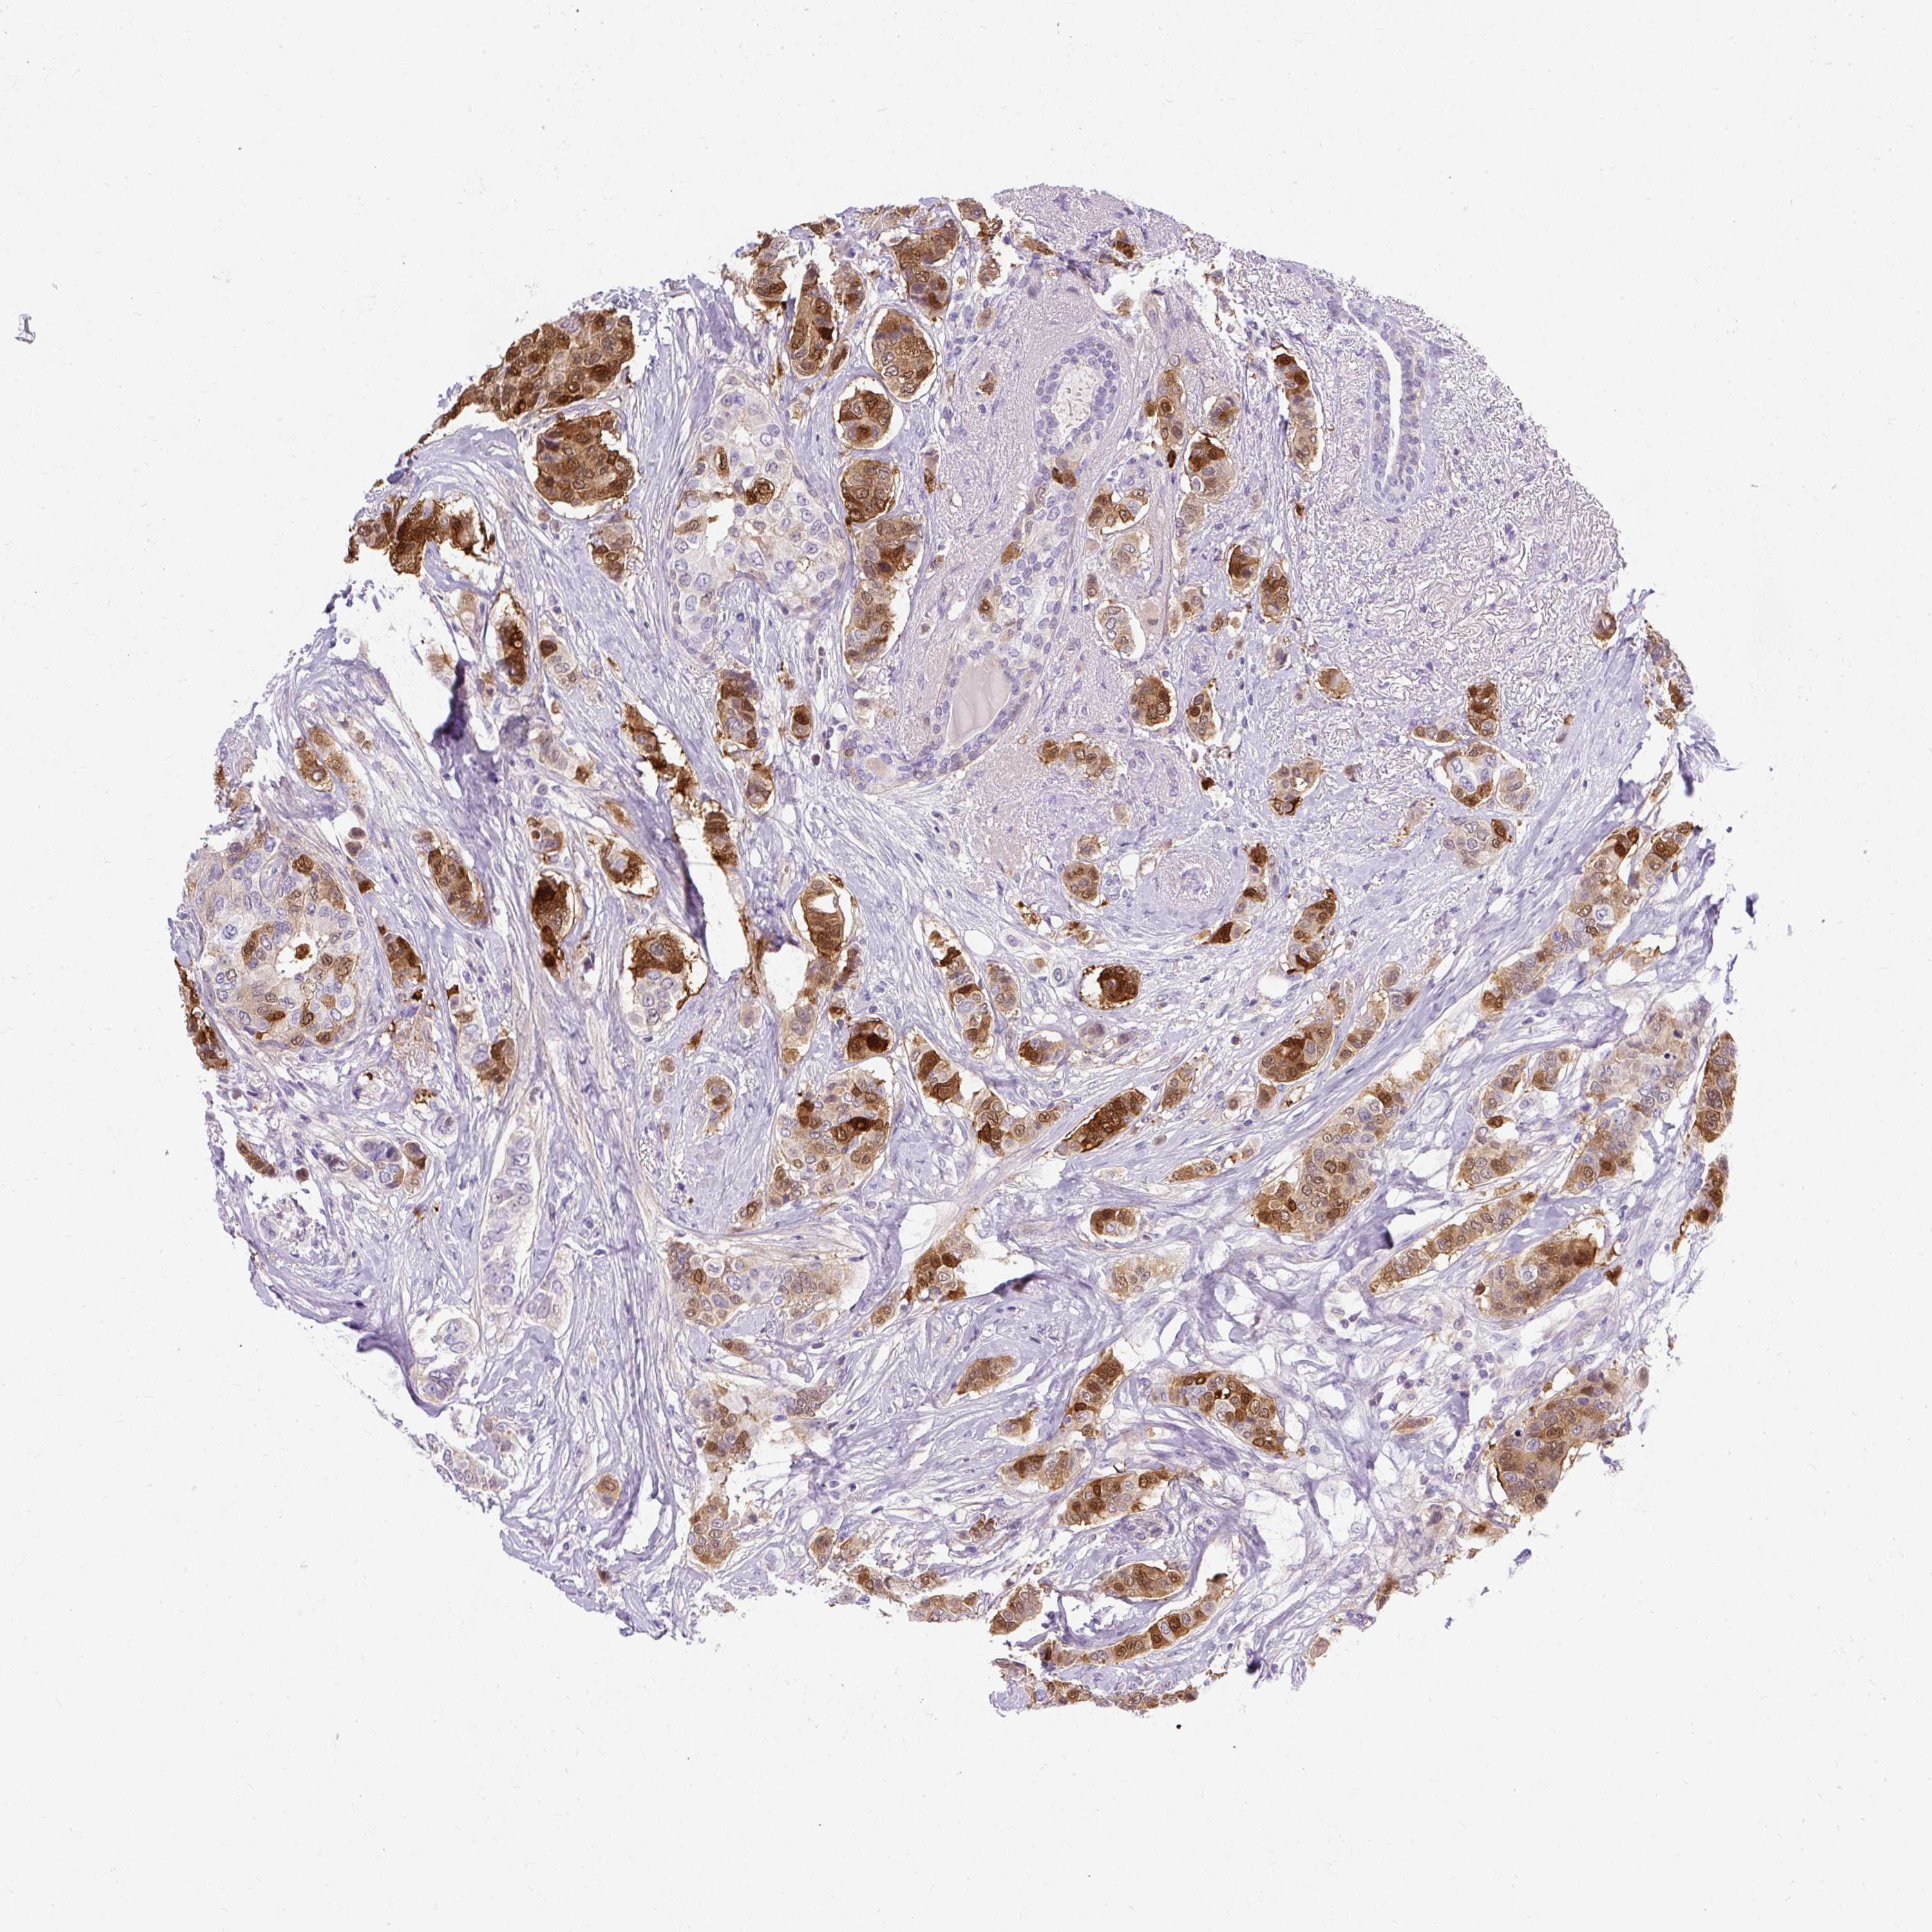

BRCA TCGA BRCA VALIDATION PROTEIN EXPRESSION

ANTIBODIES

AND

VALIDATION